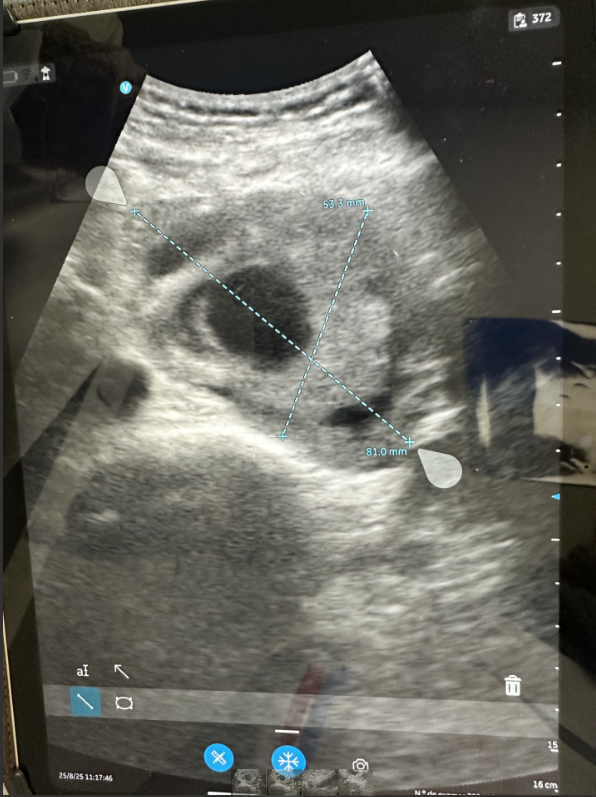

La ecografía clínica realizada en nuestra consulta de Atención Primaria mostró un aneurisma de aorta infrarrenal de 5,3 × 8,1 cm, con trombo intramural y sospecha de disección, hallazgo no presente en estudios previos.

Antecedentes de enfisema pulmonar, fumador activo, masa pulmonar cavitada en estudio, cáncer vesical tratado mediante RTU (2000), y apendicectomía. En agosto de 2024 se realizó un angio-TAC donde se identificó un aneurisma de aorta abdominal pararrenal, originado inmediatamente por debajo de la arteria renal izquierda y extendiéndose hasta 3 cm de la bifurcación aórtica, con diámetro máximo de 5,2 × 7,4 cm y trombo mural. El paciente rechazó la intervención quirúrgica propuesta tras ser informado de riesgos y alternativas.